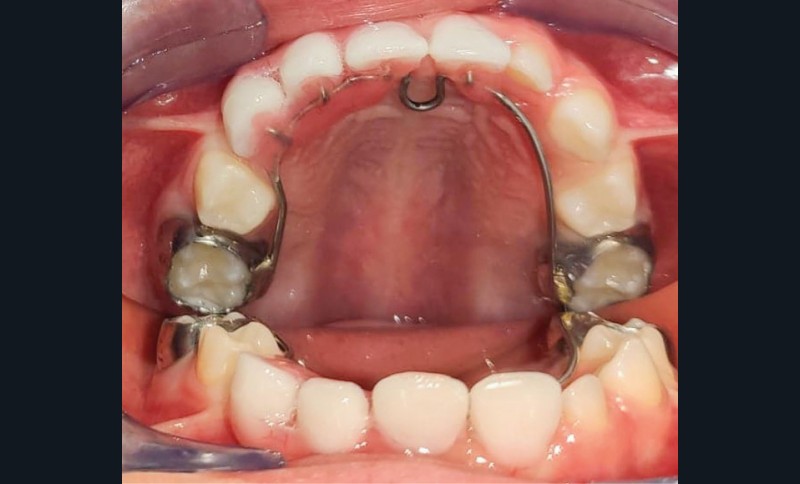

Pour les édentements limités, les dents prothétiques peuvent être fixées sur un arc palatin ou lingual, lui-même fixé sur des bagues orthodontiques ou des coiffes pédiatriques préformées (CPP) sur les secondes molaires temporaires. Ce type de mainteneurs d’espace fixe exige une hygiène buccale rigoureuse, un mauvais contrôle de plaque entraînant un risque de caries des dents porteuses des bagues ou de CPP.